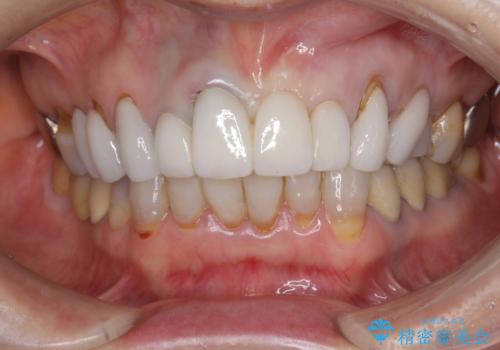

[ セラミック治療 ] 歯ぐきの際の黒ずみを改善したい

- 歯ぐきとセラミックの間の黒ずみが目立つので、きれいに治してほしい。と希望され来院されました。

歯ぐきの位置が変化しクラウン下の歯が見えるようになってしまったことで、審美障害が生じている状態です。

クラウンマージンの再設定を行うことで、黒ずんだ部分を再度覆い、審美障害を改善します。